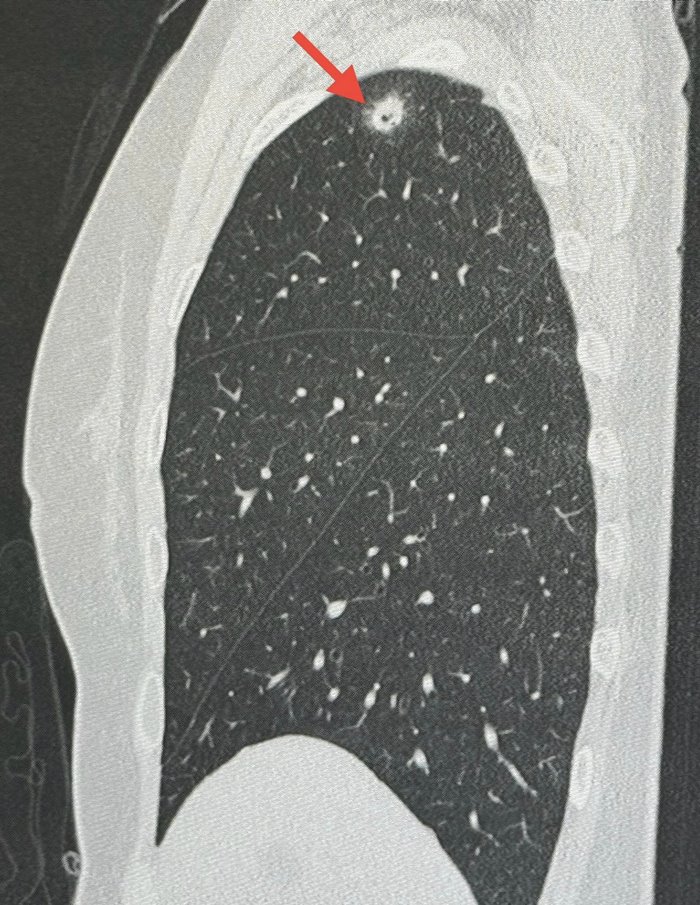

วันที่ 3 มิถุนายน 2567 นพ.มนูญ ลีเชวงวงศ์ แพทย์เฉพาะทางด้านโรคระบบการหายใจ โรงพยาบาลวิชัยยุทธ โพสต์ผ่านเฟซบุ๊ก หมอมนูญ ลีเชวงวงศ์ FC ระบุว่า พบเคสผู้ป่วยหญิงอายุ 52 ปี บ้านอยู่ กทม. ปกติแข็งแรงดี ไม่ไอ ไม่มีไข้ ไม่เบื่ออาหาร น้ำหนักไม่ลด ไม่ปวดหัว ไม่เคยสูบบุหรี่ ไม่มีโรคประจำตัว ไปตรวจร่างกายประจำปี เมื่อ 12 พฤษภาคม ที่ผ่านมา เอกซเรย์ปอดพบก้อนเล็ก ๆ เกิดขึ้นใหม่ที่ปอดขวากลีบบน

เอกซเรย์ปอดก่อนหน้านั้น 1 ปีปกติ ทำคอมพิวเตอร์ปอดพบก้อนขนาด 0.9 × 0.9 × 1.7 เซนติเมตร เห็นโพรงอยู่ข้างในก้อนที่ปอดขวากลีบบน ตรวจเลือดไม่ติดเชื้อเอชไอวี